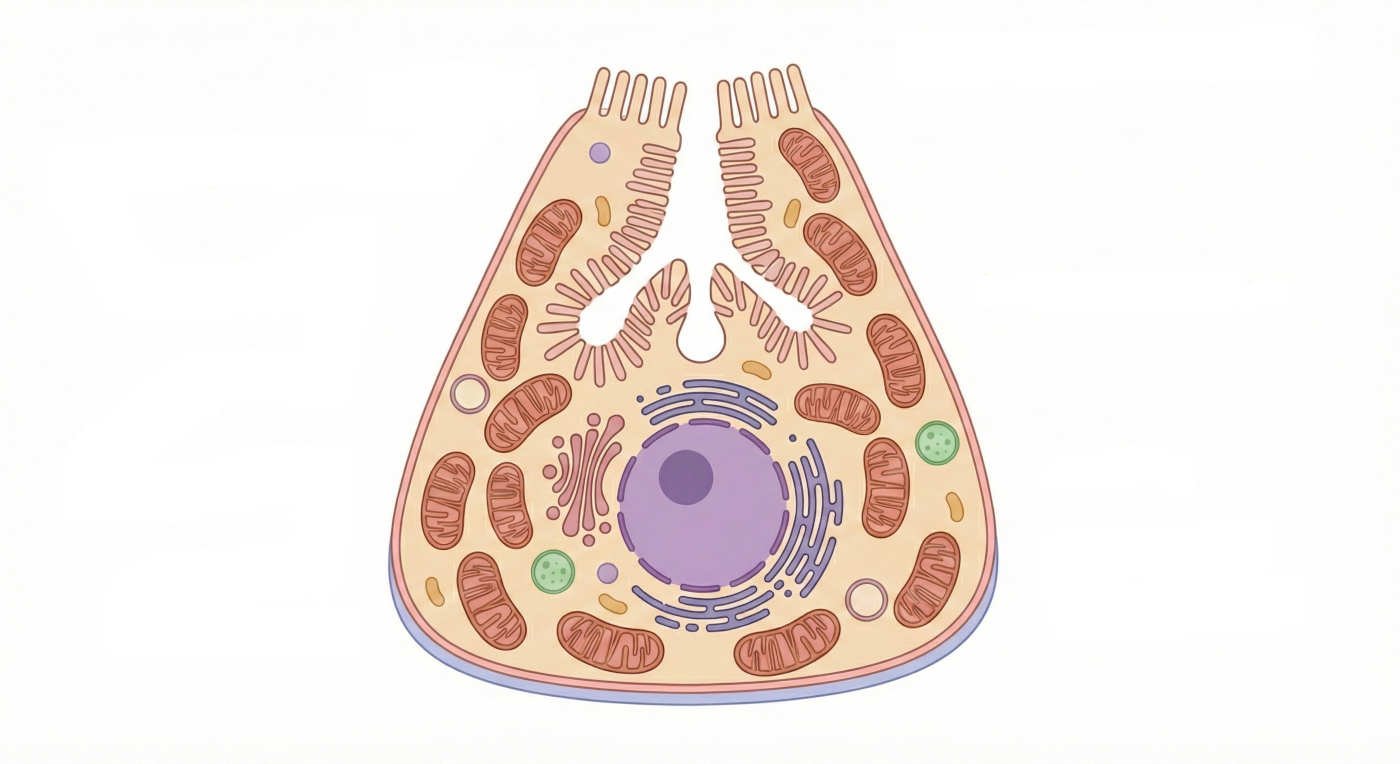

الخلايا الجدارية (Parietal Cells)

ملخص المنشور

الخلايا الجدارية (Parietal Cells) هي خلايا حيوية عالية التخصص تقع في الغدد المعدية، ووظيفتها الأساسية إفراز حمض الهيدروكلوريك (HCl) والعامل الداخلي.

تتميز هذه الخلايا بتركيب دقيق غني ...